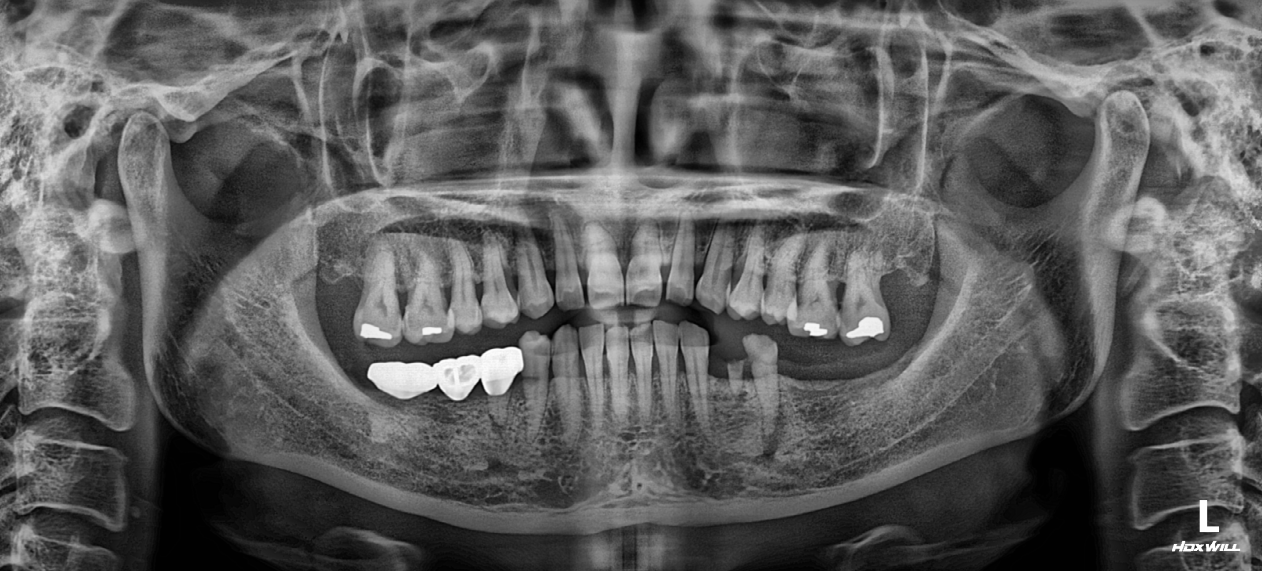

35. Comprehensive Full-Arch Transformation: Restoring Confidence in a Young Phobic Patient

Reversing the effects of generalized rampant caries and occlusal collapse in a female patient in her 20s. A tooth-preserving, implant-assisted approach focused on stable VDO elevation and overcoming social anxiety.